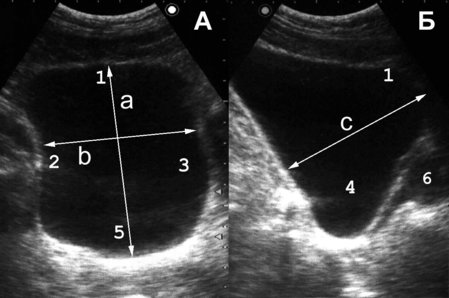

Мочевой пузырь представляет собой полый орган, расположенный в малом тазу, за лонным сочленением. Емкость пузыря от 200 до 600 мл, в патологических условиях может достигать 1000−2000 мл. У здорового человека первый позыв на мочеиспускание возникает при объеме мочевого пузыря 100−150 мл, выраженный позыв − при заполнении 250−350 мл. Анатомически в мочевом пузыре различают верхушку, шейку, дно и тело. Верхушка − место перехода пузыря в среднюю пузырно-пупочную связку, различима только при его наполнении (1 − см. рис. 1). Дно (4) − наиболее широкая нижнезадняя часть мочевого пузыря, обращенная у мужчин в сторону прямой кишки, у женщин в сторону матки и верхней части передней стенки влагалища. Шейка − суженная часть мочевого пузыря, граничит с мочеиспускательным каналом. Средний отдел, расположенный между верхушкой и дном мочевого пузыря, называется телом. мочевой пузырь имеет переднюю, заднюю и две боковые стенки (2, 3), переходящие одна в другую без четких границ. Мочепузырный треугольник Льето (5) образован устьями мочеточников и внутренним отверстием мочеиспускательного канала, основанием его является межмочеточниковая складка. Начальный отдел мочеиспускательного канала охватывается предстательной железой (6).

Рис. 1. Сонограмма мочевого пузыря мужчины в норме. Остаточный объем мочи с достаточной для практики точ¬но-стью можно определить по формуле a х b x c x 0,57 [50]. (Поперечное [A] и продольное [Б] сканирование, конвексный датчик 5 МГц, “Logiq-500”).